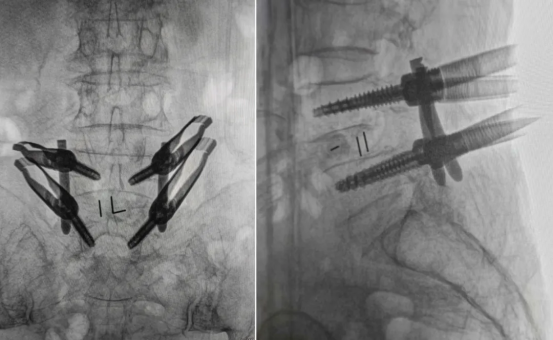

After intraoperative verification confirmed accurate positioning, four pedicle screws were placed. Compared to the traditional freehand technique, robot assistance eliminates deviations caused by reliance on subjective tactile feedback, significantly enhancing the accuracy of screw placement.

After screw placement was completed, the surgeon proceeded through the working channel to access the foraminal region. Using specialized minimally invasive instruments, the pathological disc tissue was removed to decompress the nerve root. Next, the preselected interbody fusion cage was implanted into the intervertebral space via the channel to restore disc height and reconstruct lumbar stability, creating an optimal environment for interbody fusion.

Finally, the surgeon contoured the connecting rods and introduced them through the working channel. The rods were then secured to the previously placed pedicle screws, further reinforcing lumbar stability. After confirming the correct position of the construct, the incision was closed in layers, completing the procedure.